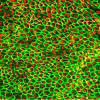

Stem cells treat macular degeneration Stem cell-derived retinal pigmented epithelial cells. Cell borders are green and nuclei are red. Credit: University of California - Santa Barbara.